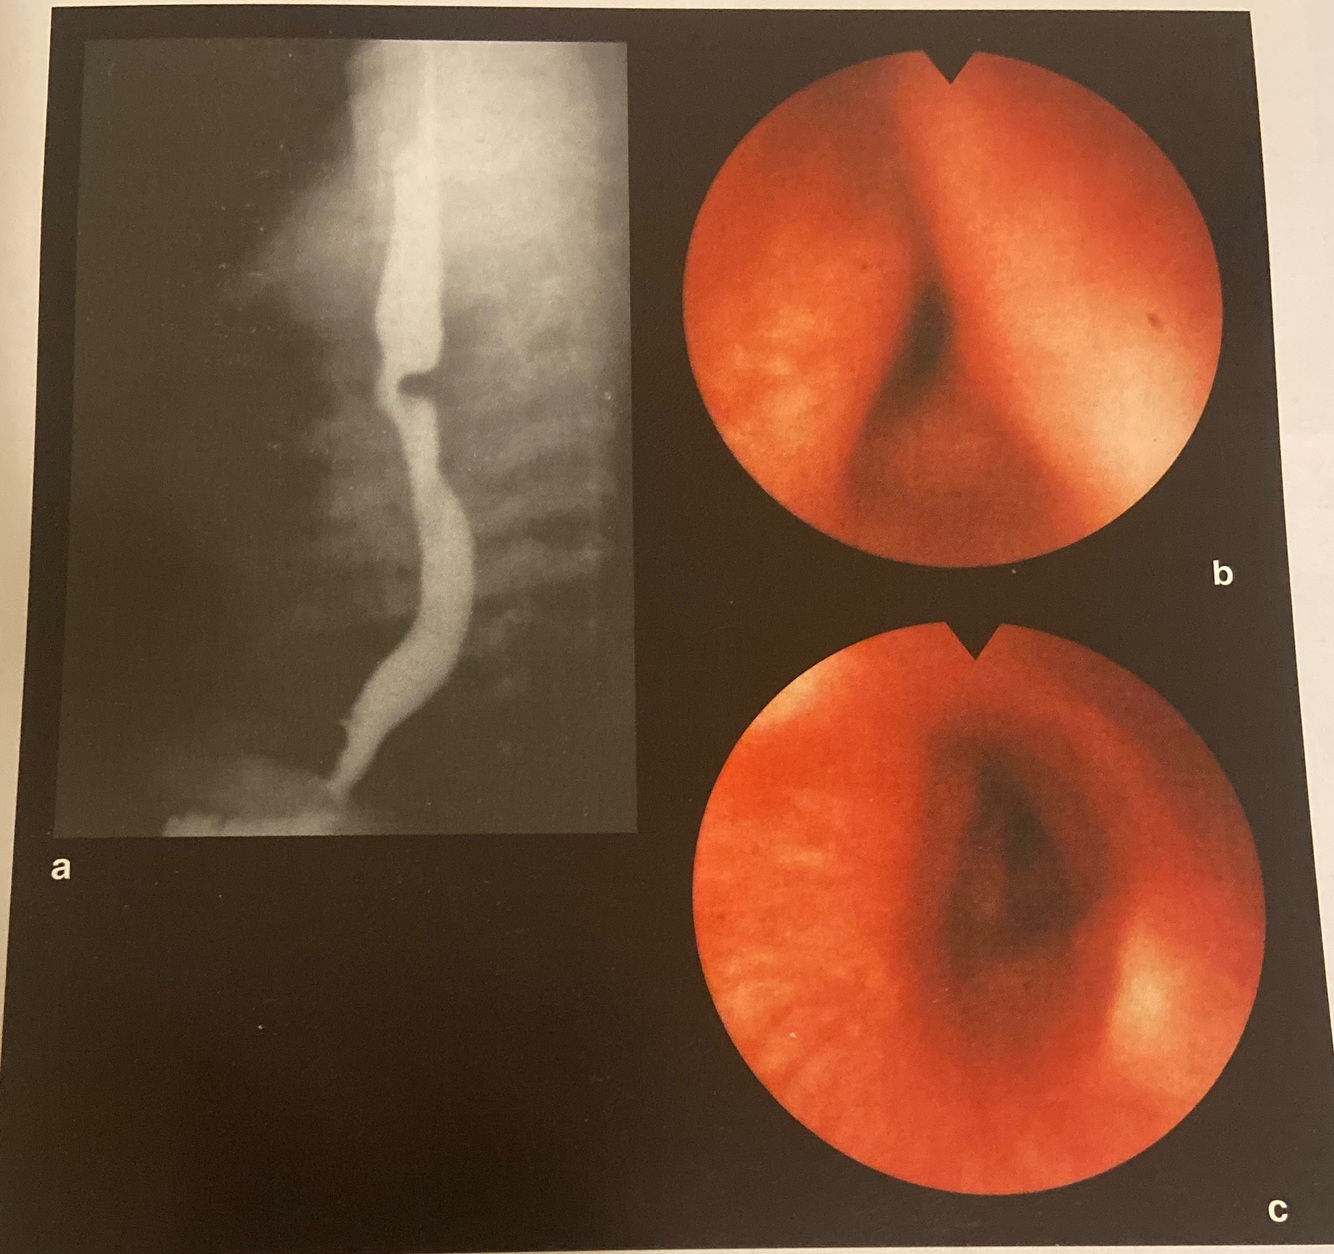

Kissing ulcers no terço médio do esôfago devido a

Nimesulida (na impressão aortica)